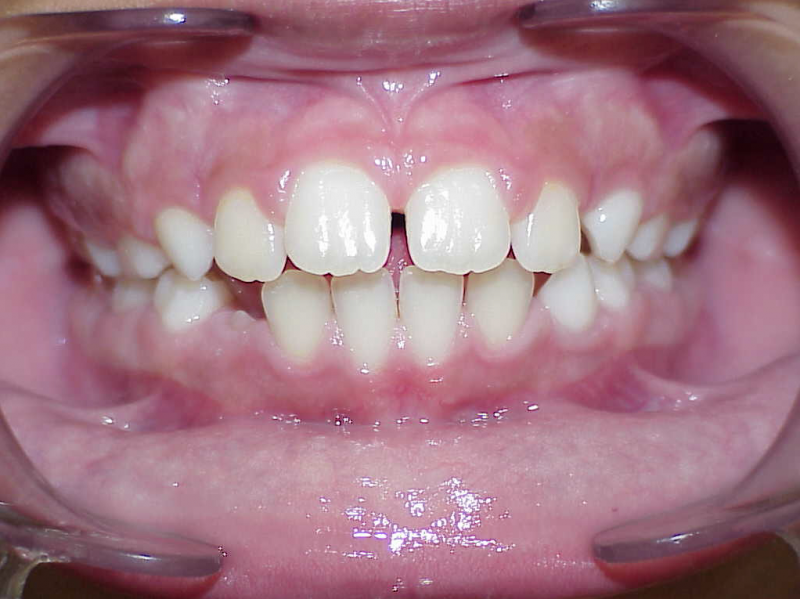

Na behandeling

14-47 maanden: Volledig banden/slotjes in de boven-en onderkaak

(omdat er hier blijvende kiezen ontbraken moesten er kiezen getrokken worden en de ontstane ruimtes gesloten, dit verklaart de langere behandeltijd)

Retentie fase: Wrap en C-CBar